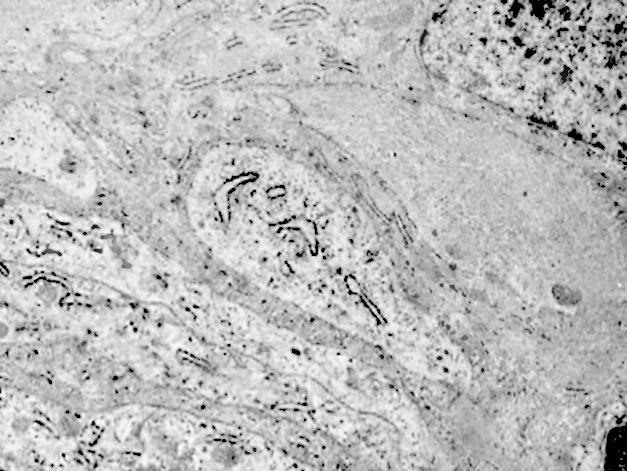

2/a AUTOFAGOSOMA

I focolai di macroautofagia possono essere presenti in zone diverse del citoplasma. La loro microstruttura di base è costituita da una area vacuolare demarcata da una membrana a doppio strato; l’area cava è occupata per quote variabili da materiale amorfo,da aggregati filamentosi,da frammenti di organuli,da gruppi granulosi, il tutto in diversi stati di conservazione. Questi focolai macroautofagici appaiono come strutture avulse dalle mutevoli condizioni bio-morfologiche del citoplasma nel quale si sono formate. E’ frequente il riscontro di cellule di aspetto cribroso per la esistenza di micro vacuoli scavati nel citosol e per la dilatazione delle cisterne del reticolo endoplasmico contengano nel citosol una formazione macroautofagica occupata in parte da materiale amorfo e filamentoso.

Non mancano elementi cellulari,forniti di un citosol contenente solo ribosomi liberi, rare strutture reticolo endoplasmatiche in via di disgregazione e molto materiale amorfo, essere occupati da un focolaio di macroautofagia con aggregati di filamenti.

Sono repertabili anche cellule meningoteliali ben strutturate e ricche di organuli marcate da un focolaio di autofagia contenente frammenti di substrutture e materiale filamentoso.

Anche a livello di prolungamenti citoplasmatici di cellule meningoteliali si riscontra la presenza di due focolai autofagici occupati in parte da materiale amorfo.